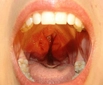

Bademciğe Ne İyi Gelir?Bademcikler, boğazın arka kısmında bulunan ve bağışıklık sisteminin bir parçası olan lenfatik dokulardır. Genellikle enfeksiyonlara karşı savunma mekanizması olarak görev yaparlar. Ancak zaman zaman bademciklerde iltihaplanma ve enfeksiyon görülebilmektedir. Bu durum bademcik iltihabı (tonsillit) olarak adlandırılır. Bademciğe iyi gelen bitkiler ve doğal yöntemler, bu rahatsızlığın tedavisinde yardımcı olabilir. Bademciği Rahatsız Eden BelirtilerBademcik iltihabının başlıca belirtileri şunlardır:

Bu belirtiler, bademcik iltihabının ciddiyetine göre değişiklik gösterebilir ve tedavi gerektirebilir. Doğal Yöntemler ve Bitkisel ÇözümlerBademciği rahatlatmak ve iltihaplanmayı azaltmak için bazı doğal yöntemler ve bitkisel çözümler mevcuttur. Bunlar arasında: